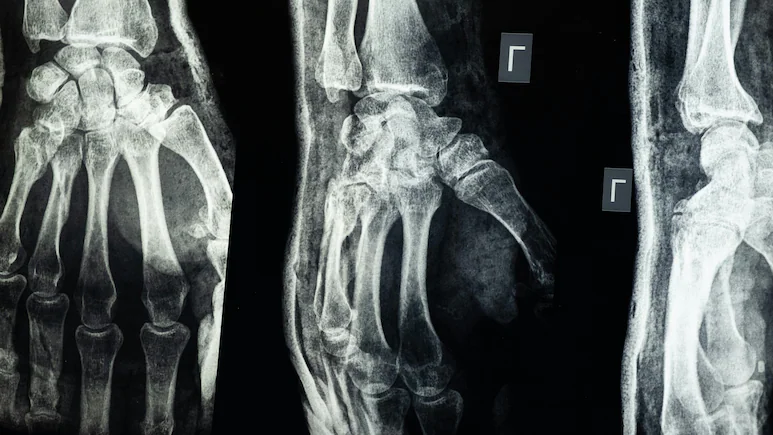

Лепилото вече е тествано върху 150 пациенти със счупвания. В един от случаите – при пациент със счупен китков став – само три месеца след процедурата рентгеновите снимки показали пълно възстановяване без усложнения.